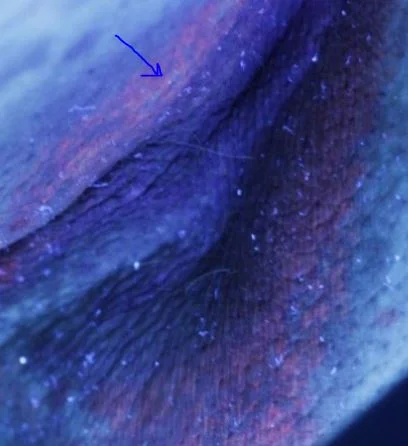

Diagnosis based on the classic “coral red” fluorescence with Woods Lamp (type of blue light).

Erythrasma demonstrating “coral red” fluorescence with woods lamp. Photo via dermnetnz.org.